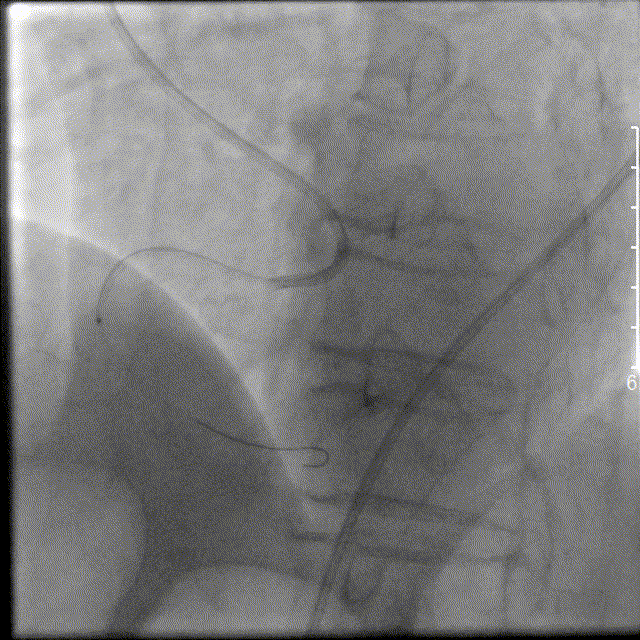

左图:LAD:LM开口至近段30%局限狭窄;LAD开口至近段40%局限狭窄,近段可见动脉瘤,中段60%局限狭窄;LCX支近段50%局限狭窄。

右图:RCA:中段完全闭塞,远端血流TIMI0级。